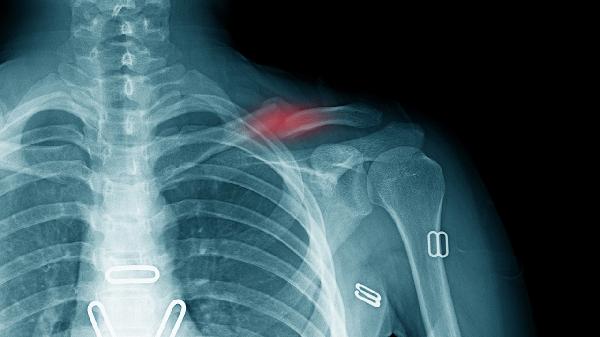

2.發(fā)病原因不同:肩周炎是指肩關(guān)節(jié)周圍軟組織的慢性無(wú)菌性炎癥,肩關(guān)節(jié)急性扭傷、軟組織勞損或退變、上肢固定過(guò)久等為該病病因;胸廓出口綜合征是指鎖骨下動(dòng)、靜脈及臂叢神經(jīng)在胸廓上口受壓而產(chǎn)生的一系列癥狀,其病因有第7頸椎橫突過(guò)長(zhǎng)、第1肋骨上移、斜角肌異常等。

3.癥狀不同:肩周炎常見癥狀為肩痛,呈持續(xù)性,氣候變化和勞累可使疼痛加重,并放射至頸項(xiàng)和上肢,但放射痛與神經(jīng)分布不一致?;颊哌€可出現(xiàn)肩關(guān)節(jié)僵硬及活動(dòng)受限,嚴(yán)重時(shí)肩部肌肉出現(xiàn)萎縮;胸廓出口綜合征可分為臂叢神經(jīng)受壓和血管受壓,當(dāng)臂叢神經(jīng)受壓時(shí),主要表現(xiàn)為患肢肩部及上肢疼痛、無(wú)力,病變?cè)缙谔弁闯书g歇性,并向前臂及手部尺側(cè)放射,嚴(yán)重時(shí)前臂及手部尺側(cè)可出現(xiàn)感覺異常,表現(xiàn)為指力減弱、精細(xì)活動(dòng)不靈活、小魚肌及骨間肌出現(xiàn)萎縮,表現(xiàn)為“爪形手”。血管受壓時(shí),患側(cè)上肢可出現(xiàn)套狀樣感覺異常,表現(xiàn)為肢體發(fā)涼怕冷、軟弱無(wú)力、顏色蒼白、遠(yuǎn)端水腫等。